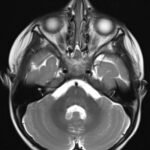

Pediatric neuroblastoma is famously characterized by an abdominal mass in a toddler with “raccoon eyes,” Horner syndrome, and/or opsoclonus myoclonus. However, rare cases may present with non-discrete symptoms and signs which create challenges for timely diagnosis. This case depicts a toddler with bulbar symptoms, including bilateral ptosis, dysphagia, drooling, head tilt and ataxia in a post-viral course mimicking other neurologic diagnoses, including myasthenia gravis. Magnetic resonance imaging (MRI) of the brain and spine uncovered a right adrenal mass along with heterogenous enhancement in multiple vertebral bodies and the clivus, consistent with metastatic disease. A diagnosis of neuroblastoma was confirmed with elevated homovanillic acid (HMA) and vanillylmandelic acid (VMA) levels and adrenal biopsy. The patient was treated with plasmapheresis for suspected paraneoplastic neurological syndrome and subsequent chemotherapy. In this case presentation, we review neurologic syndromes causing acute-onset pediatric bulbar weakness along with the patient’s key MRI findings.